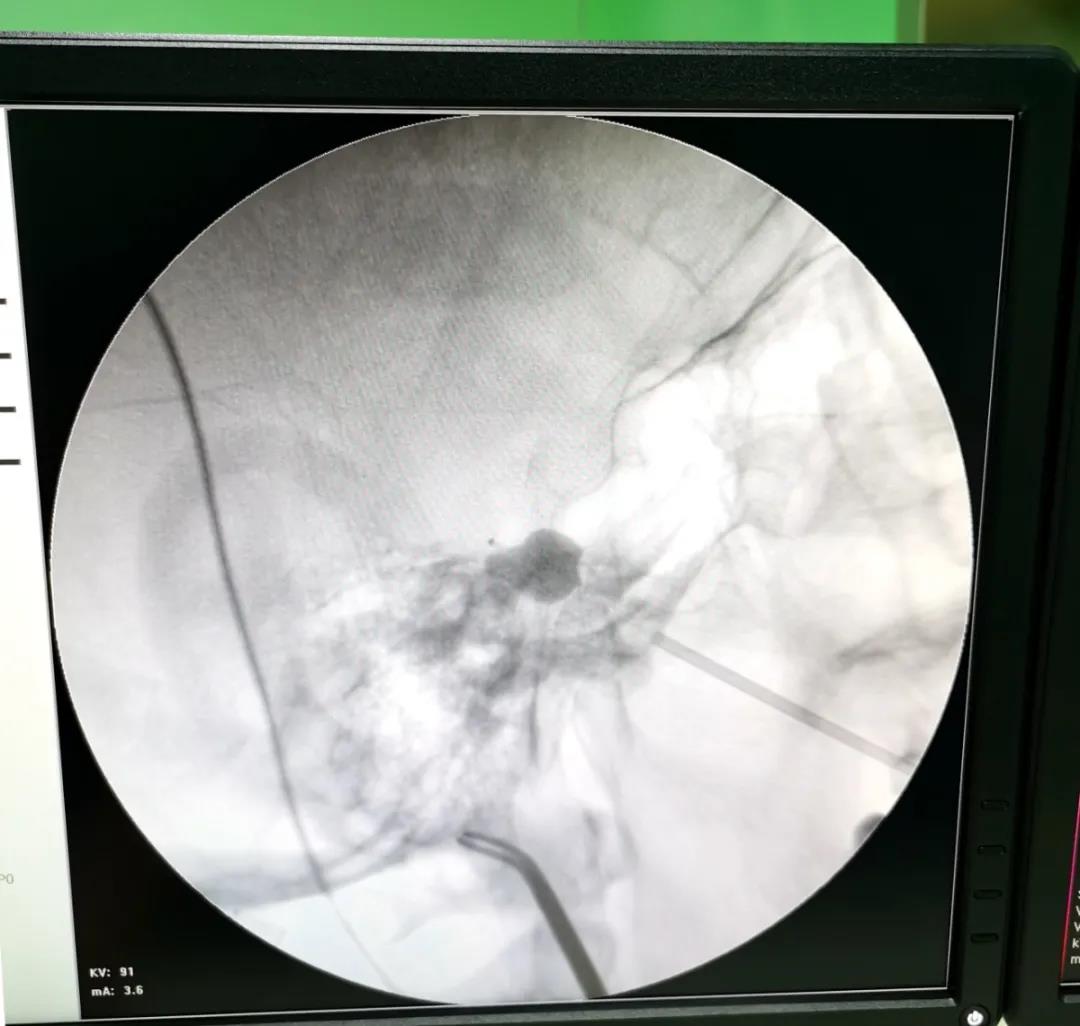

三叉神經(jīng)痛俗稱“天下第一痛”,是最常見的顱神經(jīng)疾病之一。三叉神經(jīng)痛呈刀割樣(yàng)疼痛,患者往往不敢刷牙、洗臉,痛苦不堪,嚴重影響生活質量。微球囊壓迫術作爲微創穿刺治療三叉神經(jīng)痛的重要手段,隻需通過(guò)針眼大小的創口放入穿刺針,經(jīng)口角外側用穿刺針穿刺經(jīng)卵圓孔達半月節,在半月節位置導入球囊,擴張微球囊持續壓迫3~5分鍾即可阻斷三叉神經(jīng)痛覺神經(jīng)傳導,達到治療目的。手術時(shí)間短,效果明顯,複發(fā)率低,術後(hòu)恢複快,此次手術爲該患者順利實施微球囊壓迫術,患者多年頑痛一朝解除,僅住院1-2天即康複出院。

上圖爲關慶凱副主任醫師與我院心血管内科醫護人員共同攜手打造新鄉醫學(xué)院第一附屬新華醫院三叉神經(jīng)痛微球囊壓迫術,新鄉醫學(xué)院第一附屬醫院神經(jīng)外科具有二十多年的三叉神經(jīng)診療經(jīng)驗,精通各種(zhǒng)治療方式,已取得經(jīng)治患者廣泛的認可和好(hǎo)評,歡迎廣大三叉神經(jīng)痛患者咨詢。